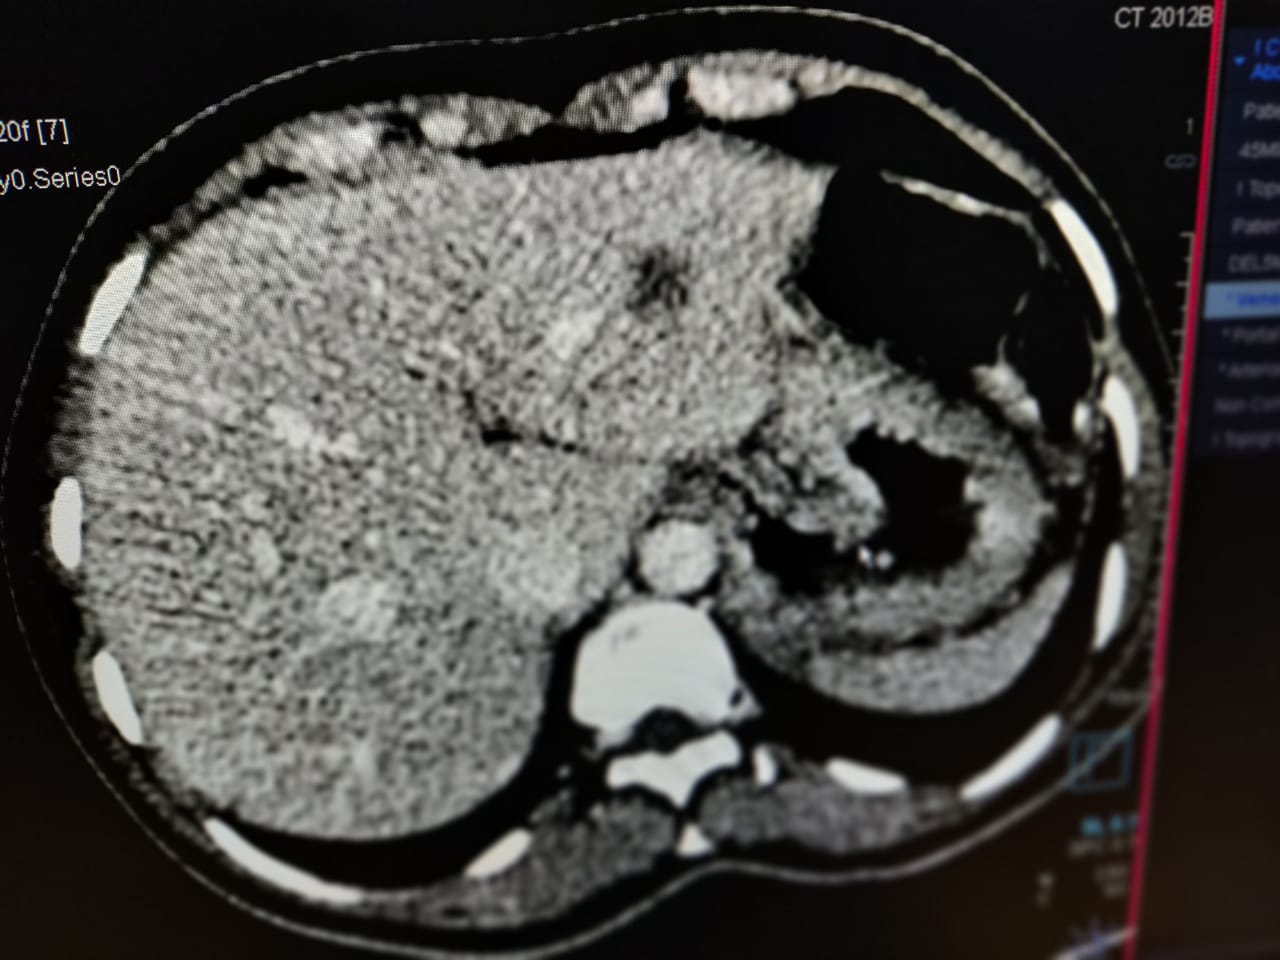

CECT revealed breast lesion extending posteriorly to involve pectoralis major muscle and metastatic lesion involving lungs, liver and lumbosacral vertebrae, making it a stage 4 breast carcinoma. []